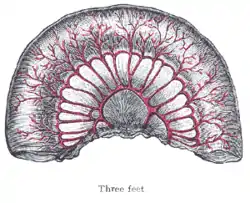

Nearest the duodenum the mesenteric loops are primary, the vasa recta are long and regular in distribution, and the translucent spaces (lunettes) are extensive.

The diagrams below show the arrangement and variations of the loops of the mesenteric vessels for various segments of the small intestine of average length: